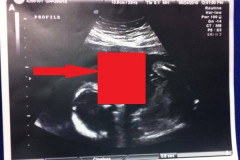

Стилист Пугачевой: «Я убрал балахоны из гардероба Аллы» (Фото и Видео) Что не так на этом фото? Самые эпические фейлы на конкурсах красоты 12 любопытных фактов, которые мы не знали об автомобилях Такими Деда Мороза и Снегурочку вы еще не видели Как уменьшить расширенные поры: 8 эффективных рецептов! Продукты, портящие зубы Она весила всего 37 килограмм и могла умереть в любой момент, а теперь посмотрит... Эти знаменитости не имеют право носить мини, так-как у них очень некрасивые ноги... Похождения золотых деток в самой строгой мусульманской стране Как молоды все были! Попробуйте узнать звезд экрана и сцены на их детских фотогр... Забавные стоп-кадры (18 фото) Они уже приготовились к похоронам своего ребенка... Но жизнь приняла неожиданный... На УЗИ видно, как малыш надувает пузырь. То, что врачи сказали матери, бросает в... Леди Гага явно пожалела о своем выборе наряда для вечернего выхода (Фото) Самый трогательный момент на армянских помолвках (Фото) Развод неминуем? Брэд Пит заявил, что с него хватит, застав Анджелину Джоли в по... Она сошла с ума! Кейтлин Дженнер снова хочет стать мужчиной потому что не может ... Если на вашей ладони есть буква М, вы — особенный человек… 14 провальных нарядов наших знаменитостей в 2015 году. Найдите им кто-то нормаль... Похождения золотых деток в самой строгой мусульманской стране (33 фото) Папина девочка. Красавицы-дочки актеров из культовых боевиков 10 шокирующих методов, которые используют интернет-маркетологи для воздействия н... Как не надо: 15 «голых» образов Дженнифер Лопес Заметите разницу? Претендентки на титул "Мисс Вселенная" с косметикой и без 20 открыток о том, что значит быть женщиной 30 фотографий, после просмотра которых вы передумаете идти на новогодний корпора... Киркоров впервые показал детей в фотосессии для журнала 5 непростительных мужских ошибок на первом свидании (7 фото) Братья И Сестры Голливуда, О Которых Вы Скорее Всего Не Знали Знаменитая модель абсолютно не стесняясь показала шрамы от увеличения груди (Фото)